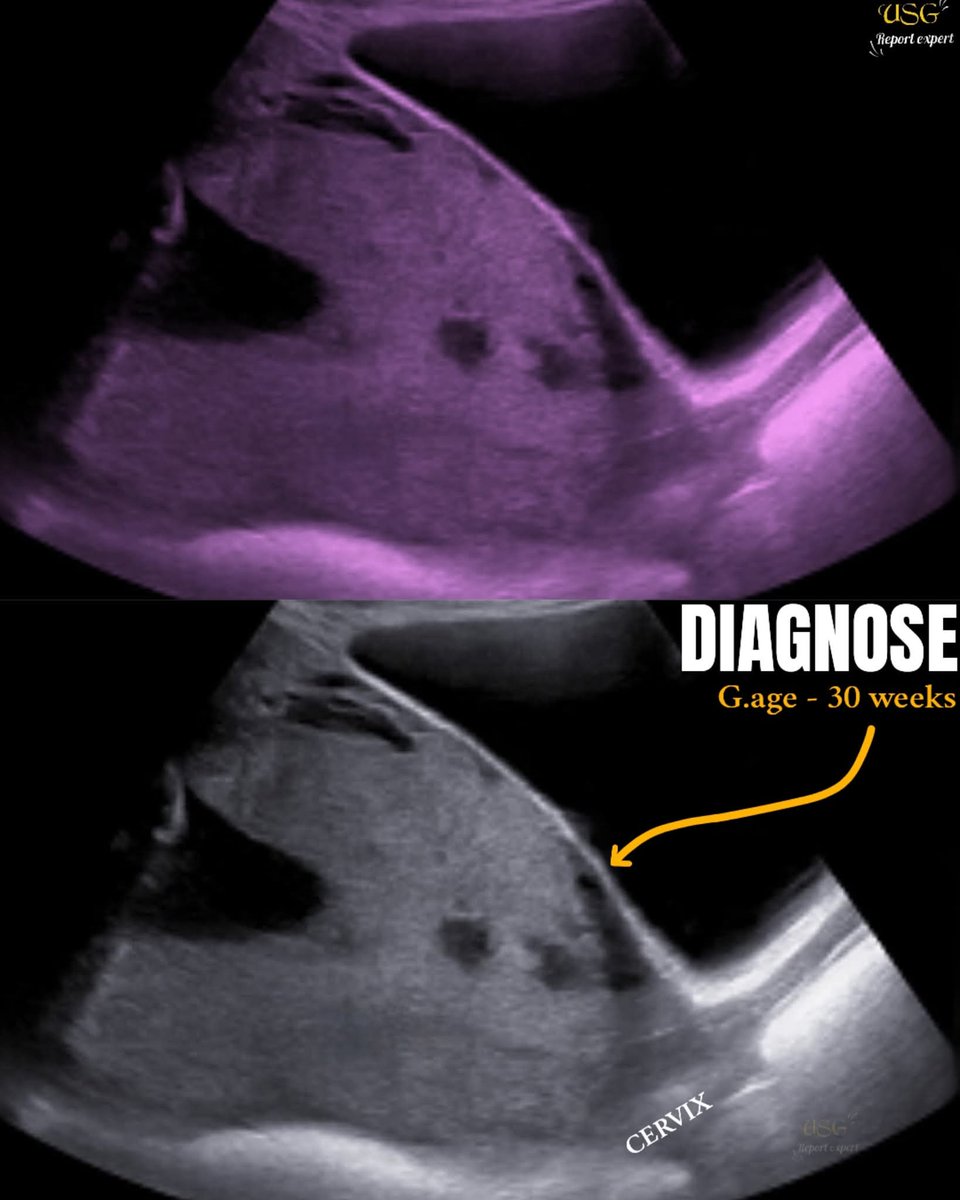

@EchoTech_4 Retroplacental space appears to be breached.

There's no color Doppler so I can't comment much on what's happening at the retroplacental zone.